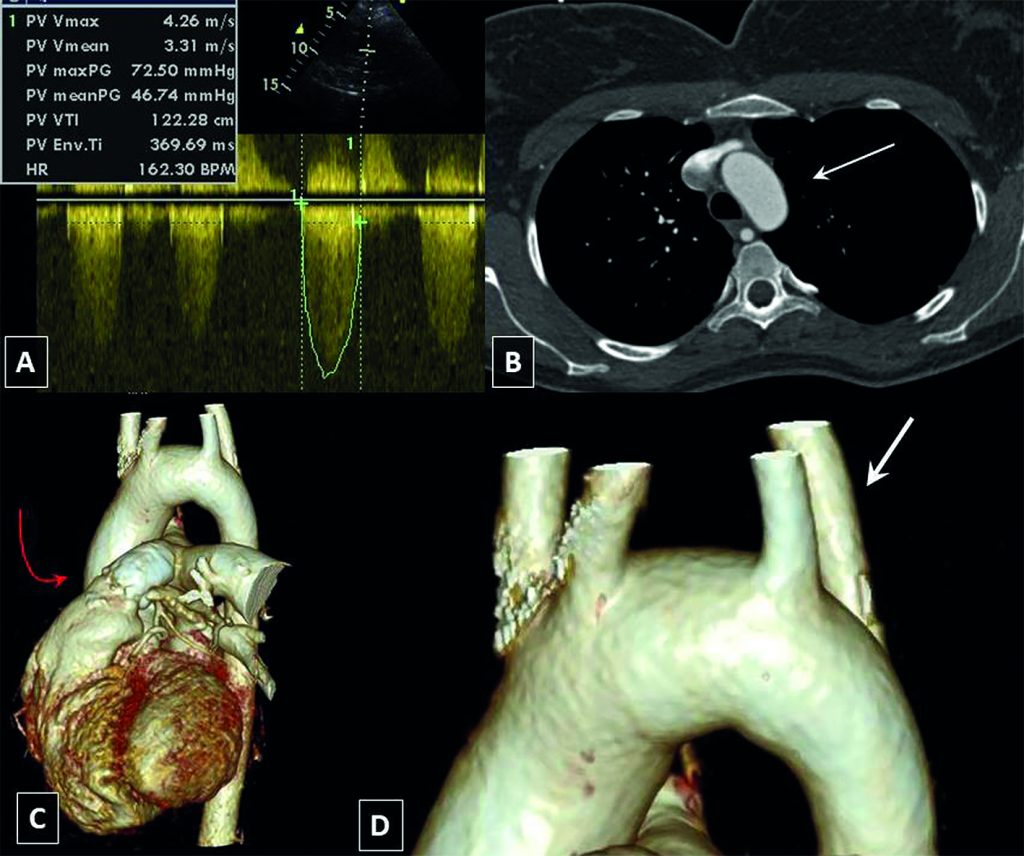

Tetralogia de Fallot Associada a Artéria Subclávia Direita Aberrante. Implicações Clínicas

Desde a primeira descrição da tetralogia de Fallot (ToF) em 1671 por Niels Stensen e em 1888 por Étienne-Louis Arthur Fallot, vários trabalhos relataram essa anomalia juntamente com suas variantes e anomalias cardiovasculares concomitantes. A artéria subclávia direita aberrante (ASDA) é a anomalia do arco aórtico mais comum. Diferentemente da artéria subclávia esquerda aberrante, a ocorrência de ASDA em pacientes com ToF só foi relatada casuisticamente. Apresentamos dois pacientes de ToF com ASDA. É importante notar que o conhecimento da coexistência das duas anomalias tem pontos muito práticos durante correções endovasculares ou cirúrgicas de defeitos cardíacos congênitos (inclusive ToF).